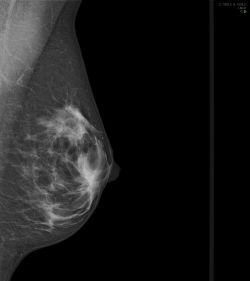

Münster (upm/kk) - Brustkrebs ist die häufigste Krebserkrankung bei Frauen. Nach Angaben des Robert-Koch-Instituts stellen Ärztinnen und Ärzte derzeit etwa 70.000 Mal im Jahr die Diagnose „Mammakarzinom“ bei einer Frau – mehr als 18.000 Patientinnen sterben jährlich an den Folgen dieser Erkrankung. Ab 2005 wurde das qualitätsgesicherte und bevölkerungsbezogene Mammographie-Screening-Programm (MSP) zur Früherkennung von Brustkrebs in Deutschland flächendeckend implementiert. Ein Forschungsteam Westfälischen Wilhelms-Universität (WWU) Münster evaluiert das Programm bezüglich der brustkrebsassoziierten Sterblichkeit - und hat dafür eine weitere große Förderung bewilligt bekommen.

Ziel des MSP ist die Senkung der Brustkrebssterblichkeit unter Minimierung der potenziellen Belastungen für die anspruchsberechtigten Frauen wie Strahlenbelastung, Überdiagnosen und Übertherapien. In diesem organisierten Früherkennungsprogramm erhalten Frauen im Alter zwischen 50 und 69 Jahren alle zwei Jahre eine schriftliche Einladung zur röntgenstrahlenbasierten Mammographie-Untersuchung. Da bei der Zulassung des deutschen MSP für eine Nutzen-Risiko-Bewertung keine nationalen Daten zur Verfügung standen und die Beurteilung nur auf internationalen Studienergebnissen aus vergangenen Jahrzehnten basierte, evaluiert ein Forschungsteam der Westfälischen Wilhelms-Universität (WWU) Münster die Wirkung dieser Früherkennungsuntersuchung auf die Brustkrebssterblichkeit in Deutschland. Das Bundesministerium für Umwelt, Naturschutz, nukleare Sicherheit und Verbraucherschutz (BMUV), das Bundesministerium für Gesundheit (BMG) und die Kooperationsgemeinschaft Mammographie fördern das Forschungsvorhaben mit rund 5,5 Millionen Euro für drei Jahre.